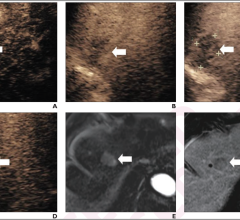

May 2, 2023 — In another first, Clarius Mobile Health, a leading provider of high-definition handheld ultrasound systems ...